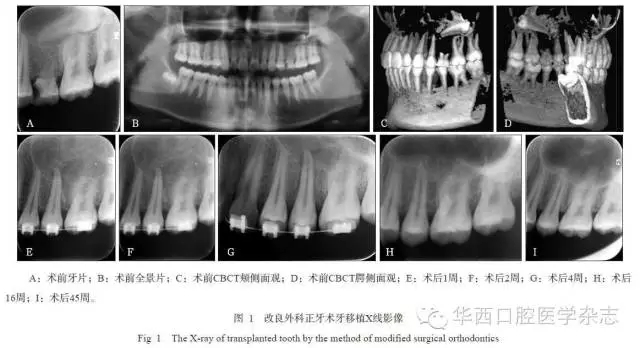

牙移植術后,均采用正畸片段弓或正畸弓絲黏接固定4~6周,術后定期隨訪6個月以上,觀察移植牙愈合狀況及X線影像改變。在術后2~12周,根據牙周愈合狀況、牙冠色澤的變化、電活力測試與X線根尖區(qū)影像等綜合評估,酌情判斷是否進行根管治療。

45例移植牙經過手術異位移植、正畸固定4~6周后,逐漸獲得穩(wěn)固,并行使咀嚼功能。經0.5~2年的隨訪觀察,34例移植牙均未出現牙根吸收、牙齒松動等并發(fā)癥,達到成功標準;11例移植牙中存在松動小于Ⅱ度、移植牙類牙周膜影增寬、牙槽骨楔形吸收、牙根吸收(但小于等于2.0?mm)等一項或幾項情況,能承擔部分咀嚼功能,達到有效標準。隨訪期內未見失敗拔牙病例。

2組移植牙術后6個月的臨床和影像結果見表1和2。統(tǒng)計分析表明:1)A、B組的松動度、根管治療比率有統(tǒng)計學差異(P=0.021, P=0.025),而牙冠色澤變化、電活力測定無統(tǒng)計學差異(P=0.225, P>0.05)。2)A、B組的移植牙根吸收、牙槽骨吸收有統(tǒng)計學差異(P=0.025,P=0.038),而牙周膜影像改變無統(tǒng)計學差異(P=0.169)(表2)。A組療效優(yōu)于B組。

已有研究[12-13]表明,影像上所觀察到再植牙的牙周膜愈合,只是一些平行于牙根面纖維的類牙周膜,與生理性牙周膜斜纖維一端埋植在牙槽骨、一端埋植在牙骨質顯然不同,理論上較難形成生理性的牙周膜愈合,或者為根與牙槽骨的直接骨性結合。牙根面外吸收,是由于牙周膜的損傷或被破壞,在感染、壞死或喪失增殖能力的牙周膜細胞引發(fā)的炎性刺激下,破骨細胞的活性增強,逐漸形成牙根和牙槽嵴吸收,最終導致移植牙松動脫落。本研究中保留了牙根周2mm左右牙槽骨,最大程度上使得牙周膜免于破壞,更有利于牙周膜愈合,從而也減少了牙根吸收。但是,單從臨床影像學上很難區(qū)分是否為真性牙周膜愈合。

另外在臨床觀察中發(fā)現,A組移植牙從臨床愈合到影像學變化,總體效果優(yōu)于B組,部分觀察指標統(tǒng)計學差異不明顯,可能與樣本量較少有關。這是因為,牙-牙槽骨聯(lián)合移植改變了單純移植牙的“牙-骨”的愈合模式,由牙根與牙槽骨難以達到的牙周膜愈合,變?yōu)檠啦酃桥c牙槽骨的“骨-骨”的愈合模式。雖然,在臨床中切取一定厚度的牙槽骨有不小難度,尤其是埋伏牙,容易出現牙槽骨與牙根的分離,其次是在顯露牙冠時易損傷牙冠釉質,但是,術前錐形束CT測量與精確定位、術中微動力和超聲骨刀精細切割、術后口腔衛(wèi)生維護,以及醫(yī)生嫻熟的技術和豐富的臨床經驗等,有助于移植手術的成功[3,14]。